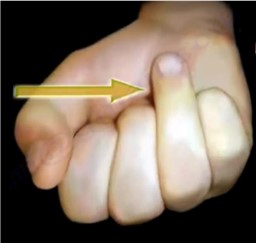

ناتوانی در خم کردن ارادی بند آخر انگشت یک نشانه تشخیصی مهم برای jersey finger است، زیرا نشان دهنده از دست رفتن عملکرد این عضله می باشد( شکل ۱).

شکل ۱ . Jersey finger، مطابق تصویر فرد در خم کردن بند آخر انگشت ناتوان است.